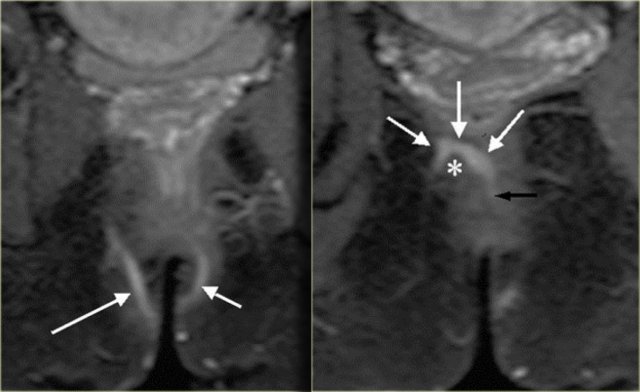

Perianal fistula: axial T2WI without fatsat (left) and with fatsat (right) Perianal fistula: axial T2WI without fatsat (left) and with fatsat (right)

T2W images without fatsat better display the anatomy, while the fatsat images better depict the fistulas.

On the left an axial T2WI and T2WI + fatsat of a transsphincteric fistula.

The defect through the internal and external sphincter at 6 o'clock is clearly visible and more apparent on the fat sat images.

Transsphincteric fistula with sphincter defect at 11 o'clock Transsphincteric fistula with sphincter defect at 11 o'clock

On the left axial T2W-fatsat images of a transsphincteric fistula with the mucosal opening at 11 o'clock.